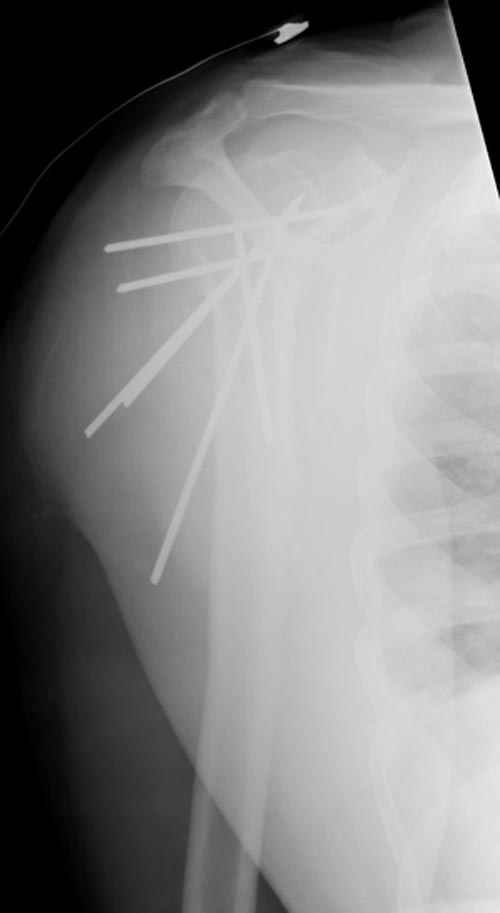

Спасибо за участие в дискуссии -перелом шейки плеча, для себя я прояснил многие технические моменты...

Посылаю послеоперационные Рг граммы.

Поздравляю, получилось просто замечательно. Если можно, расскажи чуть подробнее, как делали - как вправляли, как вводили спицы, поворачивали ли их?

Спасибо за поздравления:-))

Я и сам доволен результатом. В предпоследнем письме я кратко описал ход операции - закрыто репонировать не удалось( 2 недели с момента травмы и 1 неделя после неудачной репозиции) после удаления пучков спиц, пришлось сделать - 2см разрез на уровне перелома и с помощью периостального элеватора (золотое правило механики) *одеть* головку на дистальный отломок.

Спицы проводил через старые отверстия, вращая пучок импактором- направителем при его введении в головку.